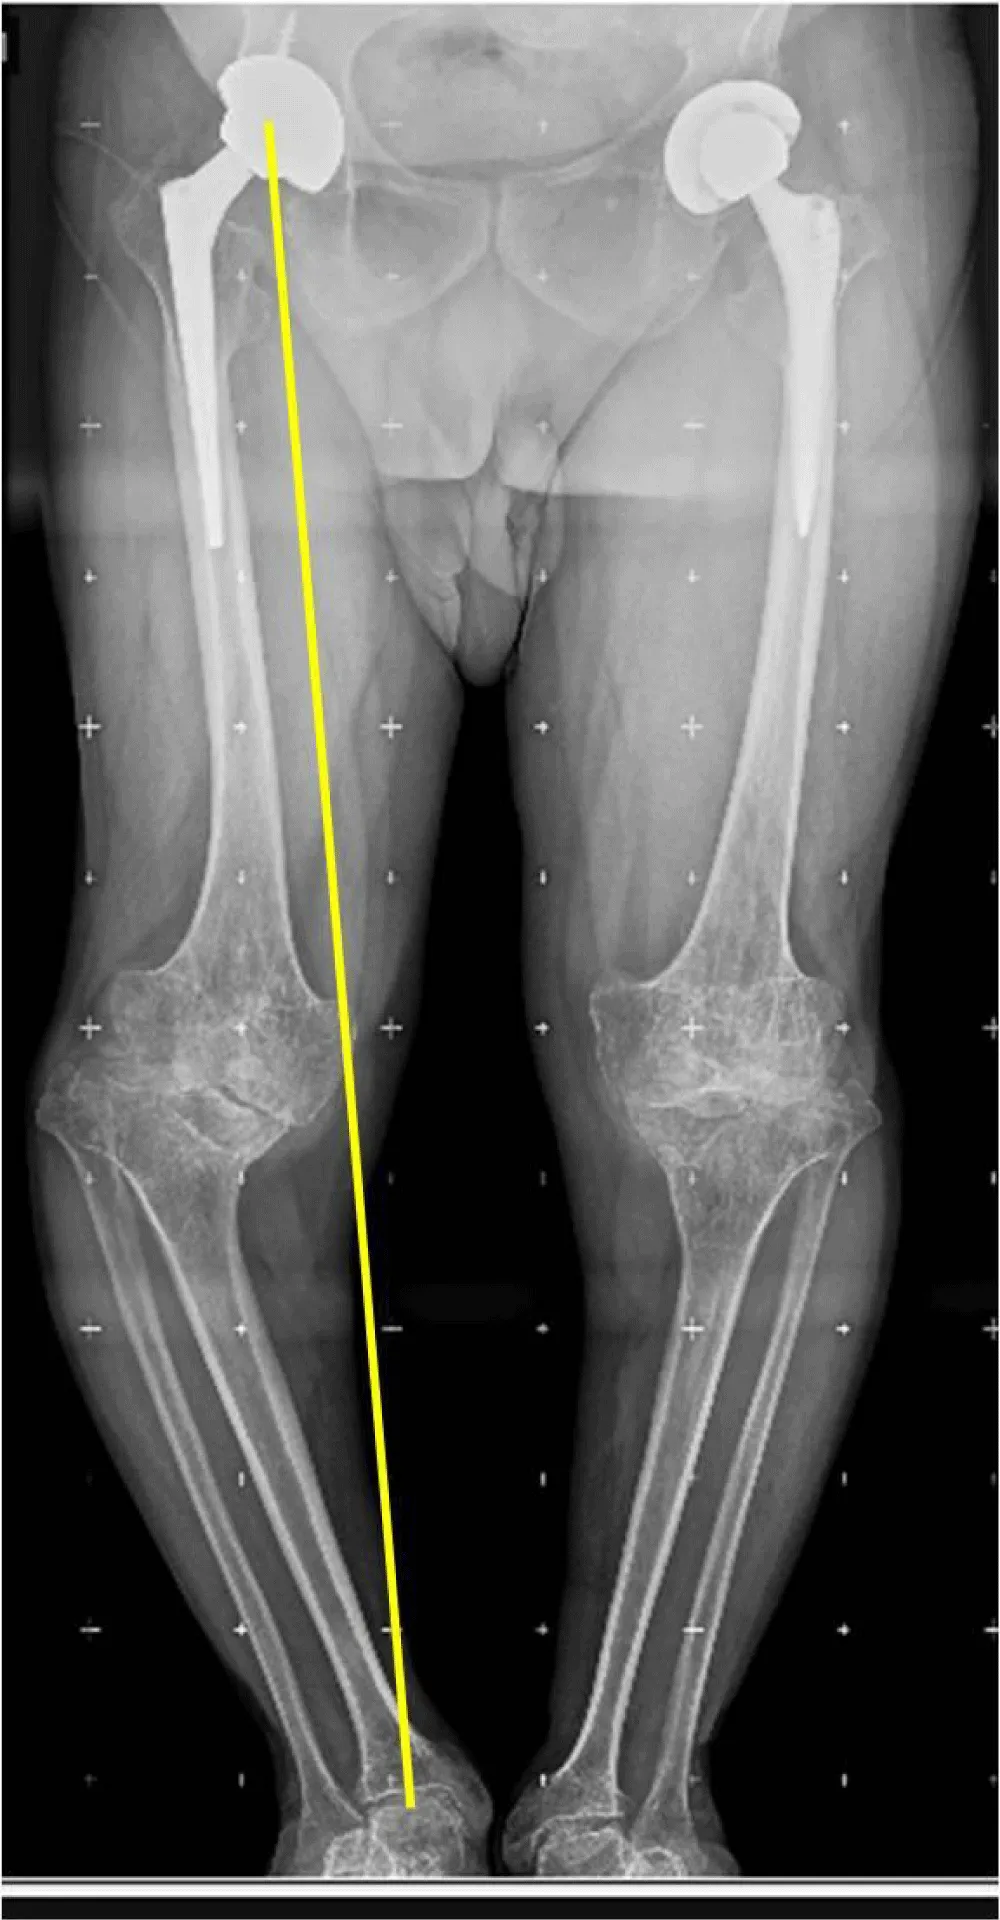

Twelve months postoperatively, the patient was able to walk without pain or the need for external assistance. The patient’s range of motion was acceptable, with active extension of 0° and flexion of 90°. The radiological evaluation revealed the absence of radiolucent lines or migrations of prosthetic components, along with consolidation of the fracture line distal to the femoral stem (Figure 9). With two years of follow-up, the patient is leading an active life without significant limitations due to his knee surgery, and is highly satisfied with the clinical outcome.